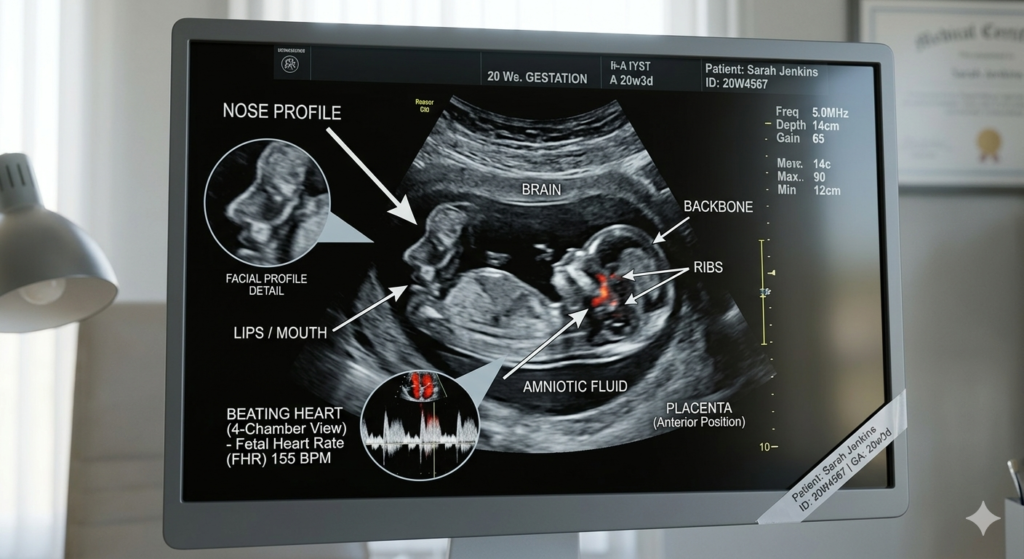

For many, the 20 weeks pregnant ultrasound (the “Anatomy Scan”) is the highlight of the second trimester. This is a 30-to-60-minute head-to-toe examination.

What the Doctor is Looking For:

- The Heart: Checking all four chambers and the major arteries.

- The Brain: Ensuring the symmetry of the cerebral hemispheres.

- The Spine: Looking for proper alignment of every vertebra.

- Placenta Position: Ensuring the placenta isn’t blocking the cervix (a condition known as placenta previa).

Real Mom Experience: “During my 20 weeks pregnant ultrasound, my baby was being so shy! I had to drink a cold glass of orange juice and walk around for 10 minutes to get them to flip over so the technician could count all ten toes. Seeing that tiny spine for the first time made everything feel so real.” — Jessica, 20 weeks.